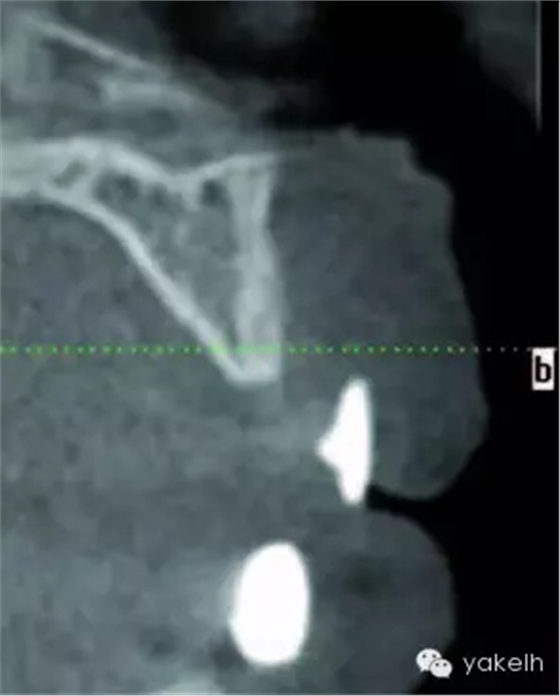

¤¤全景片以及根尖片可用于評估骨缺損、周圍的牙列以及局部解剖形態(tài)。計算機斷層攝影(CT)對骨缺損的三維觀察十分有用,也能用于評估口內(nèi)供骨區(qū)的情況??山Y(jié)合使用種植設(shè)計軟件與CT掃描,更加精確地評估患者所需重建的骨量。使用計算機掃描制備頜骨的立體光刻模型,以制訂進一步計劃。臨床醫(yī)生通過對架研究模型及診斷蠟型的研究分析,來把握牙槽嵴形態(tài)與預(yù)期修復(fù)結(jié)果的關(guān)系[7]。它們也可用于CT掃描中X線模板的制備[8]。該模板阻射影的輪廓,提示了修復(fù)體在殘余牙槽嵴斷層掃描的位置(圖13.1,圖13.2)。這有助于決定所需移植骨的大小以及取骨的部位。在骨移植手術(shù)中,設(shè)計預(yù)期修復(fù)體位置的模板,對于移植物植入位置的確定以及完成骨移植的要求也是很有用的。

圖13.1 上頜骨外傷的患者,戴入含鋇的X線檢查模板。

圖13.2 X線模板的CT掃描,模板輪廓提示了預(yù)期修復(fù)體位置與殘余牙槽嵴的位置關(guān)系。